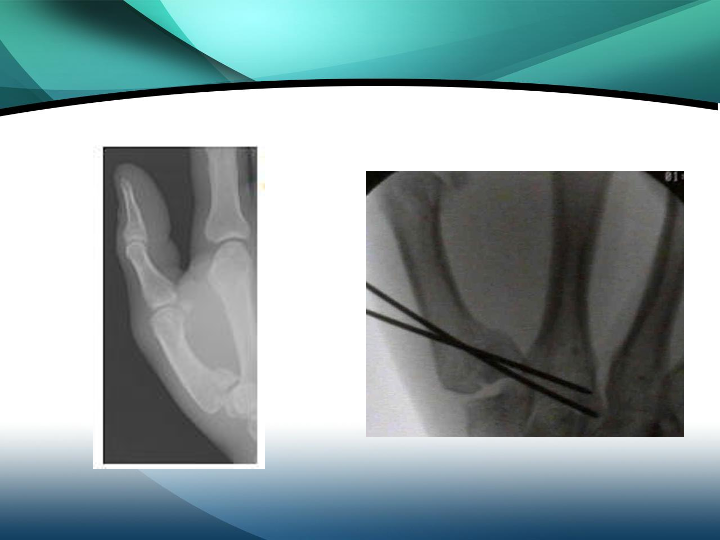

掌骨骨折